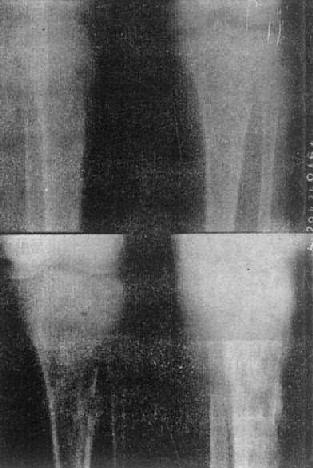

关节破坏——膝关节结核

图2-1-14 关节破坏——膝关节结核

膝关节关节间隙变窄,关节面边缘有虫蚀状骨破坏